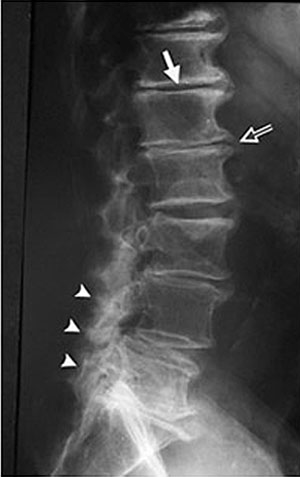

People often say to me that the GP has diagnosed 'spondylosis'. It's like we have just been told we caught a disease or something that has suddenly come on.